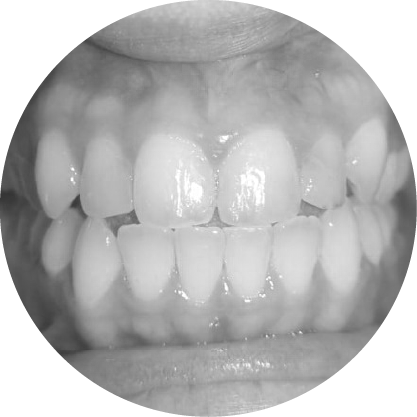

ฟันล่างยื่น (รีเวอร์ส โอเวอร์เจ็ต)

การแก้ไขฟันสบล่าง เพื่อความมั่นใจและการใช้งานที่มีประสิทธิภาพ

ฟันสบล่างคือภาวะที่ฟันล่างยื่นออกมามากกว่าฟันบน ซึ่งมักส่งผลต่อการเคี้ยวอาหารและความสมดุลของใบหน้า การจัดฟันสามารถช่วยปรับแนวขากรรไกรให้ถูกต้อง ช่วยเพิ่มทั้งประสิทธิภาพในการใช้งานและความสวยงามของใบหน้า

ตัวอย่างในชีวิตจริง